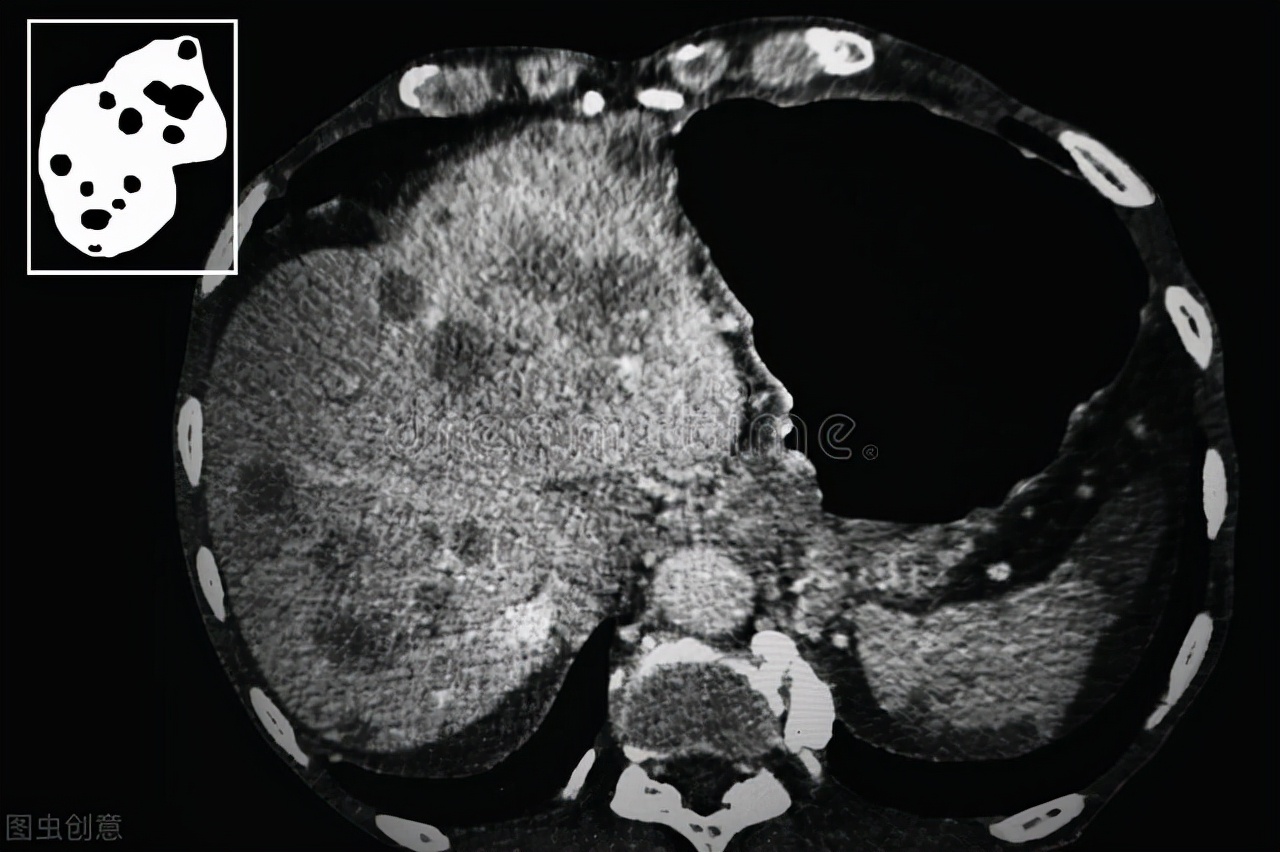

据扬州晚报的报道,63岁的黄大爷在某次健康体检中被查出肝癌,到台州市中心肝胆外科进行进一步检查,发现肿瘤直径在4cm左右,暂未发现转移。

然而血液检查中黄大爷血小板低(正常人的1/3不到),也就是说,黄大爷有自发性出血的危险,这意味着黄大爷无法做切除手术,就连微创、微波消融手术都存在极大的危险。

短时间内血小板数值很难达到理想值,可是肿瘤还是要尽快处理的,那怎么办?对此肝胆外科与介入中心的医生一同商讨对策,提出了一个最适合黄大爷的治疗方案——介入治疗。

传统手术是直接切除肿块,而介入手术则是堵上肝癌病灶的血管,让肝癌细胞“断供”,癌细胞组织没有养分补充最后自己“饿死”。

黄大爷的介入手术历经一个半小时就结束了,术后第二天黄大爷饮食就恢复正常,术后第五天就出院了。术后一个月复查各项指标均正常,肿瘤病灶无复发迹象,肿瘤大小也在不断变小。

所谓的“饿死肿瘤细胞”其实是一种介入治疗的效果,复旦大学附属中山医院介入科主任颜志平介绍,目前介入治疗的武器包括消融以及栓塞、经动脉的化疗灌注,而肝癌的介入治疗也分为两类:

第一种就是“饿死肿瘤”,经动脉化疗栓塞肿瘤动脉血管,通过阻断肿瘤血供使肿瘤组织缺血坏死,如今该方法已经成为治疗中晚期肝癌的金标准。

第二来就是直接攻击肿瘤组织,介入医生将化疗药直接打到患者的肿瘤部位,化疗药物发挥作用后直接攻击肿瘤细胞组织,另外还可以通过内照射精准的定位来把肝癌肿瘤射杀。